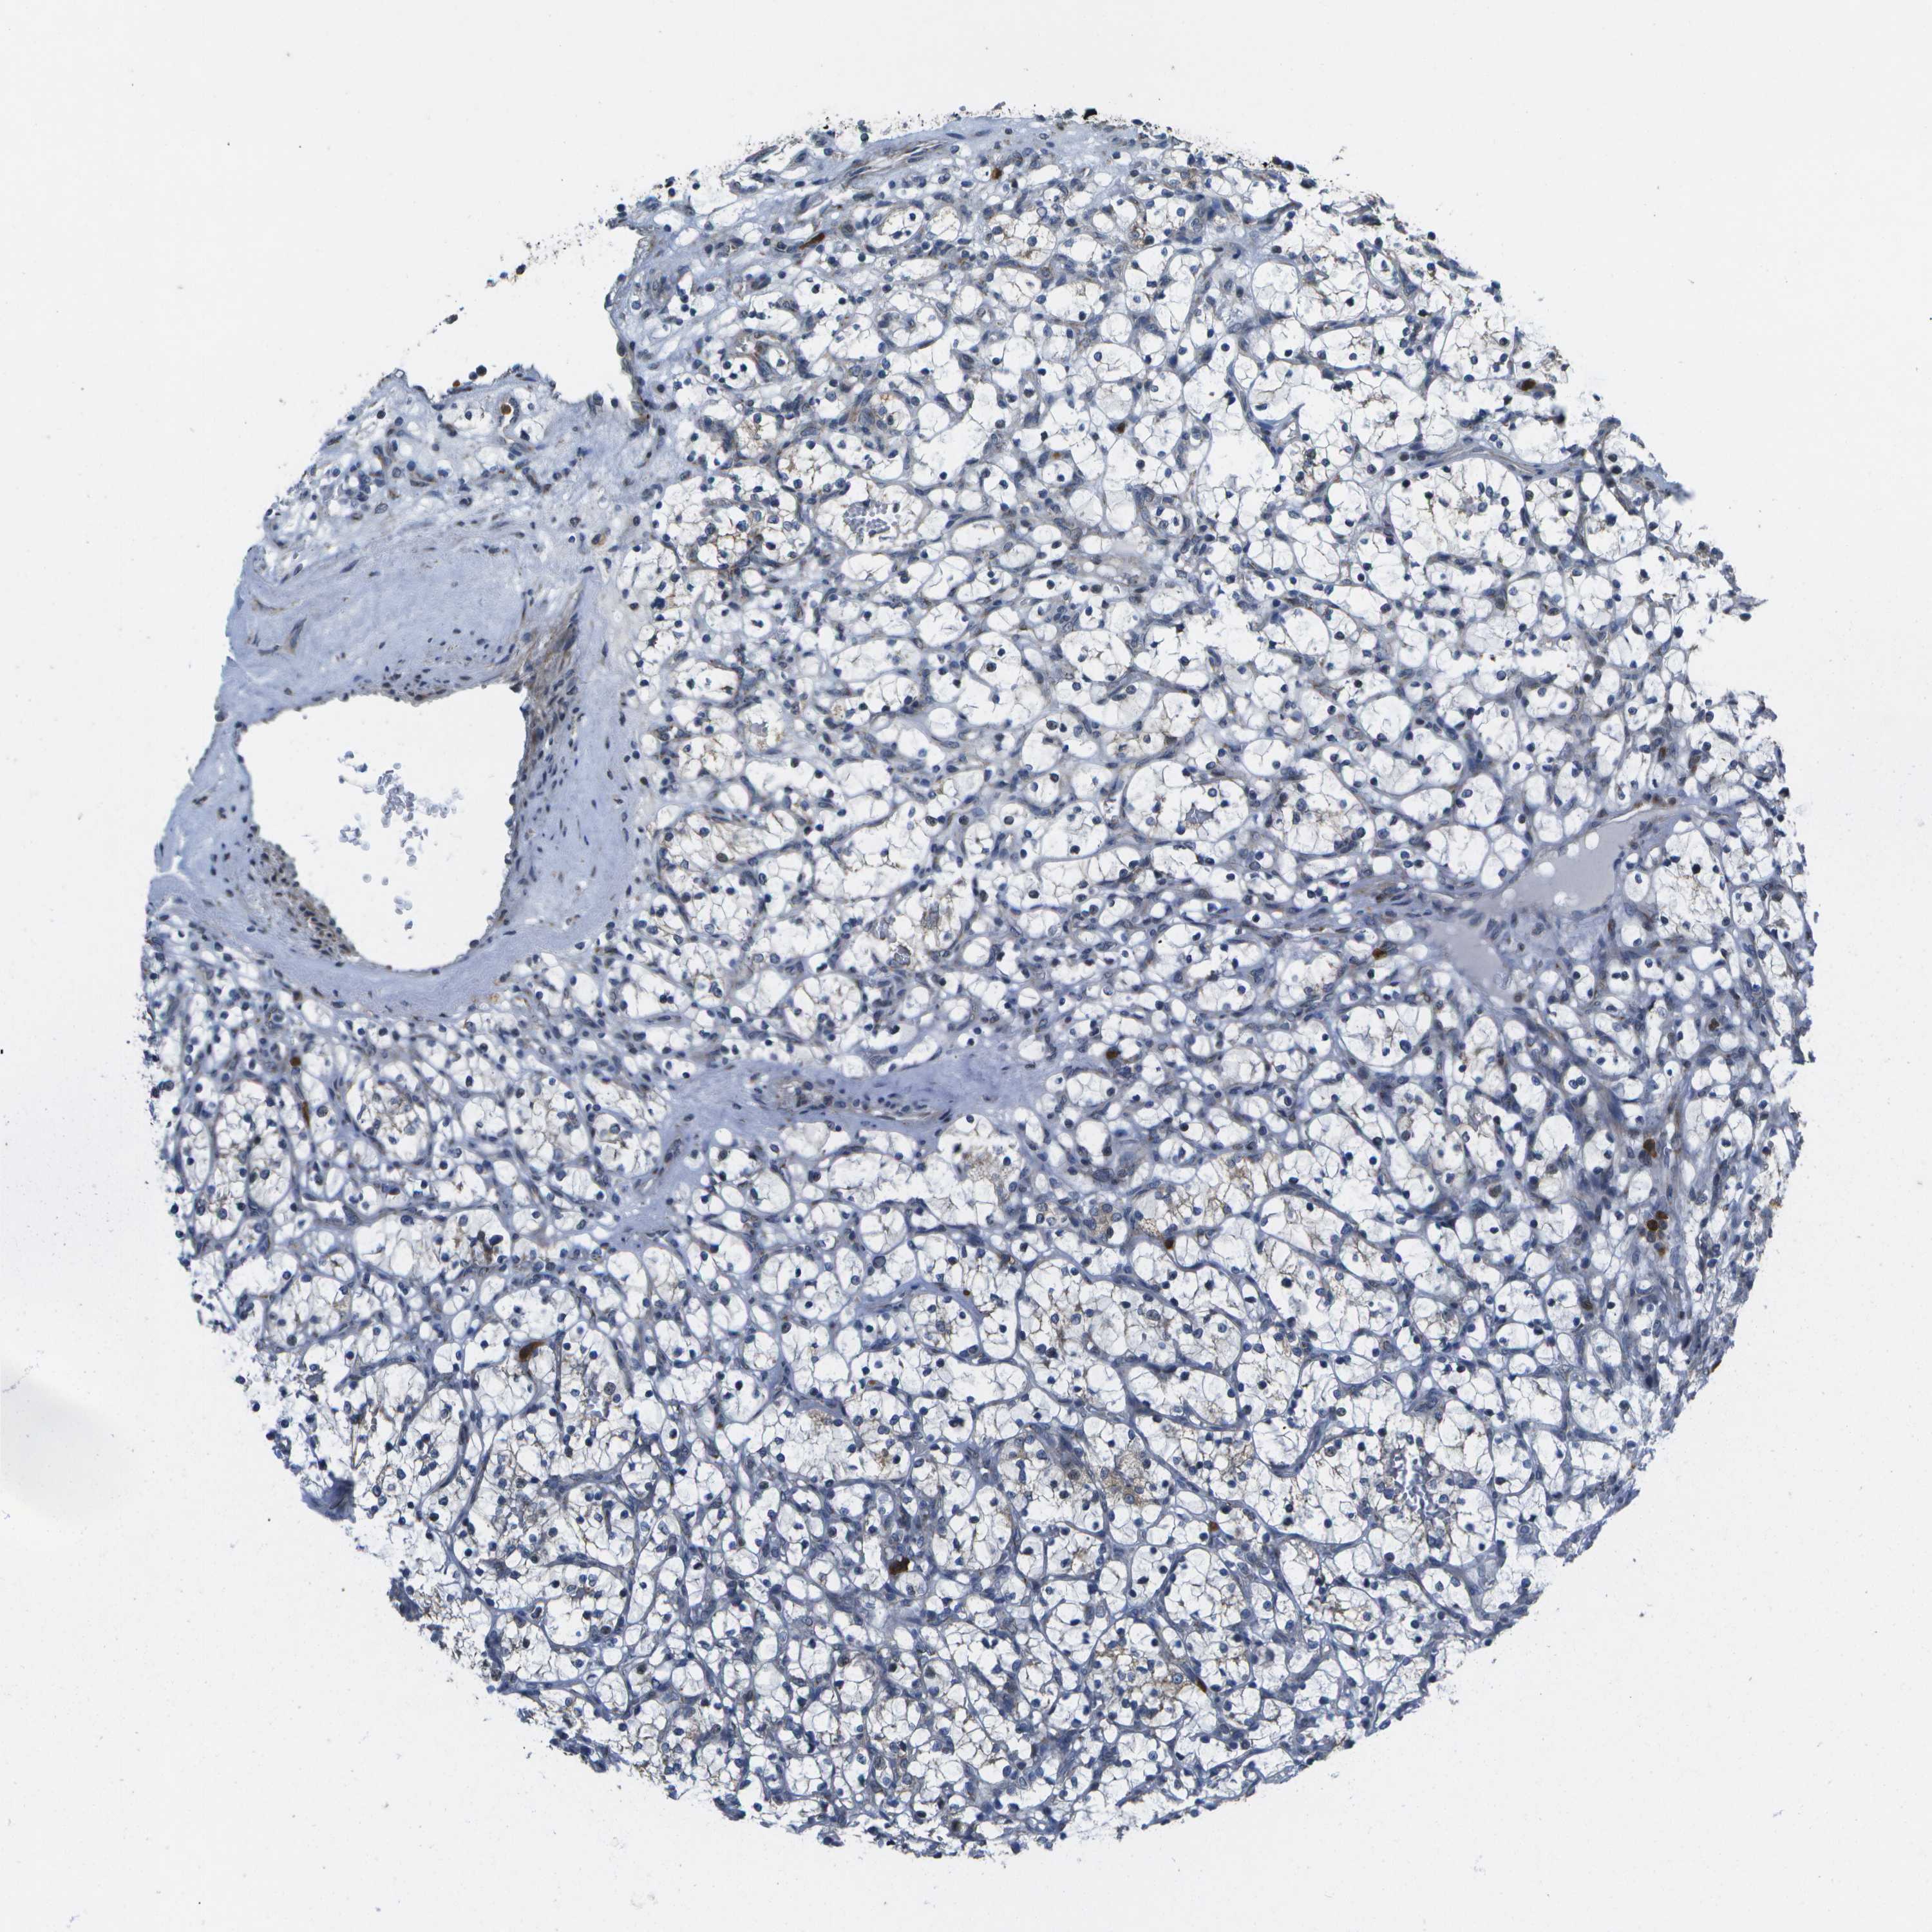

KIDNEY RENAL CLEAR CELL CARCINOMA (VALIDATION) - Interactive survival scatter ploti

The Survival Scatter plot shows the clinical status (i.e. dead or alive) for all individuals in the patient cohort, based on the same data that underlies the corresponding Kaplan-Meier plots. Patients that are alive at last time for follow-up are shown in blue and patients who have died during the study are shown in red.

The x-axis shows the expression levels (FPKM) of the investigated gene in the tumor tissue at the time of diagnosis. The y-axis shows the follow-up time after diagnosis (years). Both axes are complimented with kernel density curves demonstrating the data density over the axes. The top density plot shows the expression levels (FPKM) distribution among dead (red) and alive patients (blue). The right density plot shows the data density of the survived years of dead patients with high and low expression levels respectively, stratified using the cutoff indicated by the vertical dashed line through the Survival Scatter plot. This cutoff is automatically defined based on the FPKM cutoff that minimizes the p-score. The cutoff can be changed by dragging the vertical line or by entering a cutoff value in the square labeled "Current cut-off".

Under the Survival Scatter plot the p-score landscape (black curve; left axis) is shown together with dead median separation (red curve; right axis). Dead median separation is the difference in median mRNA expression between patients who have died with high and low expression, respectively. It is calculated as follows: median FPKM expression of dead patients with high expression - median FPKM expression of dead patients with low expression. This is intended to aid the user in visually exploring custom cutoffs and the associated p-scores and dead median separation.

Individual patient data is displayed and can be filtered by clicking on one or more of the category buttons on the top of the page. Categories describing expression level and patient information include: high, low, alive, dead, female, male and tumor stages. The scale of the x-axis can be toggled between linear and log-scale by clicking on the "x log" button. Mouse-over function shows TCGA ID, patient information and mRNA expression (FPKM) for each patient.

& Survival analysisi

Kaplan-Meier plots summarize results from analysis of correlation between mRNA expression level and patient survival. Patients were divided based on level of expression into one of the two groups "low" (under cut off) or "high" (over cut off). X-axis shows time for survival (years) and y-axis shows the probability of survival, where 1.0 corresponds to 100 percent.

GALNT15 is not prognostic in Kidney Renal Clear Cell Carcinoma (validation)

: 4.73

Average pTPM 14.6

Number of samples 100